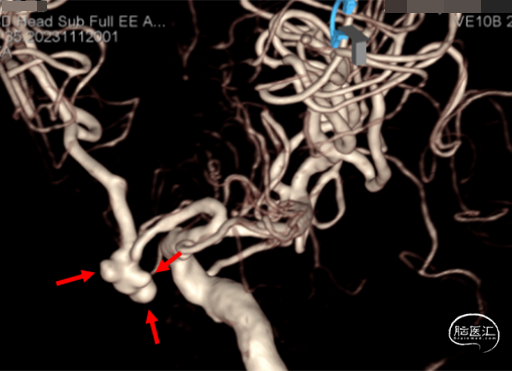

脑血管造影及3D重建示前交通动脉瘤,大小约7.6*5.2*4.8mm,瘤颈宽3.8mm,3个子瘤分别朝向不同方向,瘤颈处子瘤朝向对侧上方,考虑为动脉瘤破裂处。